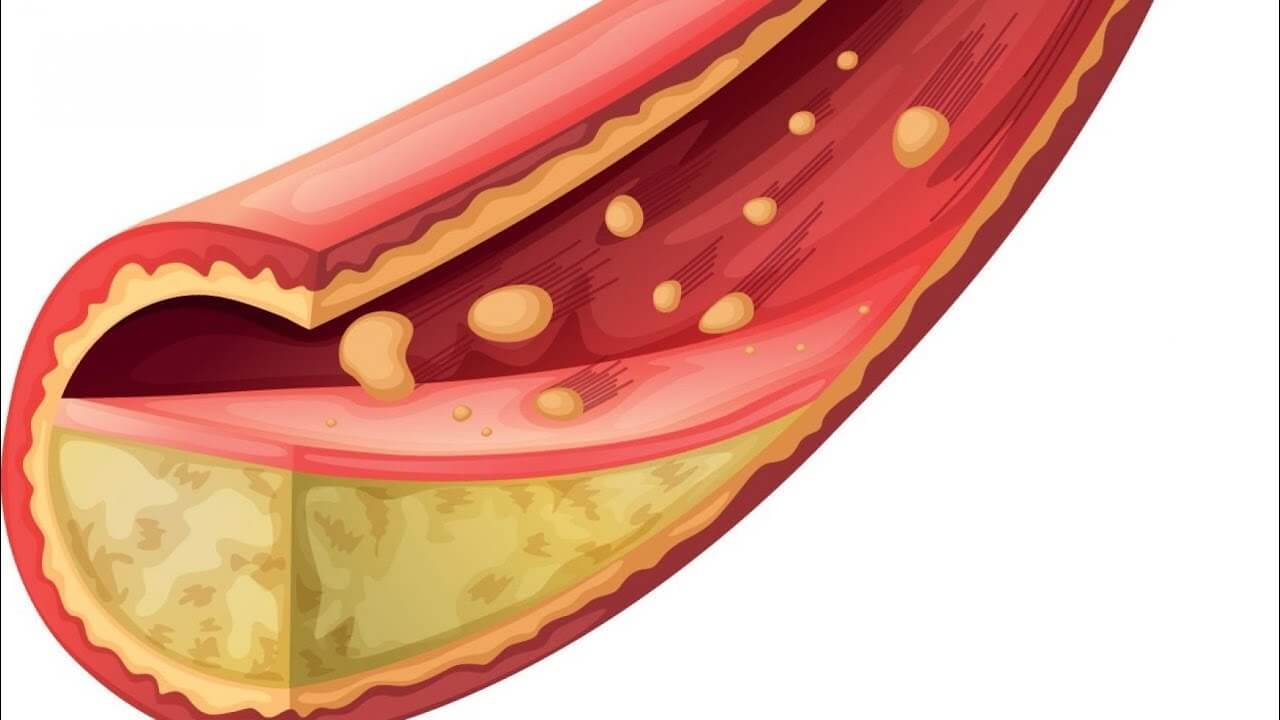

الكوليسترول هو مادة دهنية طبيعية موجودة في الدم، لها دور حيوي في بناء الخلايا وإنتاج بعض الهرمونات الضرورية للجسم. ولكن عندما يتجاوز مستواه الحد الطبيعي، يمكن أن يصبح مشكلة صحية خطيرة. ارتفاع الكوليسترول قد يؤدي إلى تراكم الدهون في الأوعية الدموية، مما يزيد من خطر الإصابة بأمراض القلب والشرايين مثل النوبات القلبية والسكتات الدماغية.

الكوليسترول الضار (LDL):

يُعرف بالكوليسترول السيئ لأنه يسبب تراكم الدهون على جدران الشرايين، مما يؤدي إلى تضييقها وزيادة خطر الإصابة بأمراض القلب والسكتات الدماغية. ارتفاع مستوى هذا النوع يشكل خطرًا صحيًا كبيرًا.